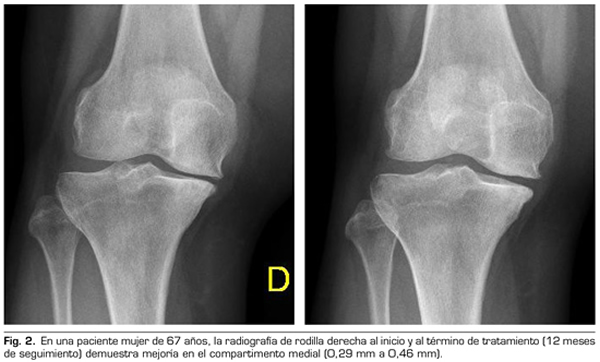

9.	Fernández-Cuadros ME, Pérez-Moro OS, Albaladejo-Florín MJ. Knee osteoarthritis: Condroprotector action and symptomatic effect of ozone on pain, function, quality of life, minimal joint space and knee arthroplasty delay. Middle East J Rehabil Health Stud. 2017;4(1):e43200. DOI: 10.17795/mejrh-43200.